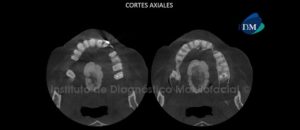

Paciente femenino, de 73 años de edad es referido al Instituto de Diagnóstico Maxilofacial (IDM) por motivos prostodónticos. La paciente es edéntula parcial bimaxilar la